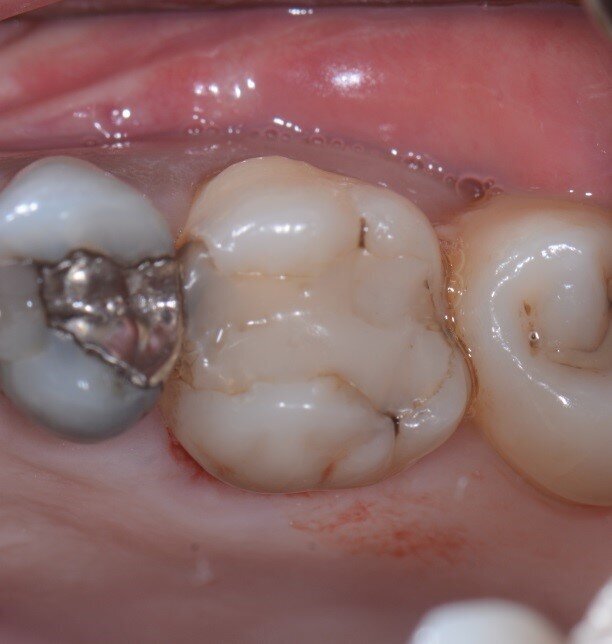

La tecnica dell’inibizione periostale modificata (MPI) mira non solo a mantenere intatta la corticale vestibolare impedendo al periostio di intervenire sulla guarigione della ferita, ma anche ad aumentarne lo spessore incollando in singolo o doppio strato una lamina corticale soft spessa 0,5 mm (Osteobiol, Tecnoss). L’utilizzo della lamina corticale suggerisce l’applicazione di questa tecnica anche nei casi in cui il piatto vestibolare fosse in tutto o in parte assente. Il caso mostrato in questo articolo rappresenta il pilota di una modifica della tecnica di inibizione periostale: è pertinente all’estrazione di un primo molare superiore destro a causa di un riassorbimento interno che rendeva il dente non trattabile (Figg. 1a, 1b), la cresta alveolare presentava un sottile strato di osso corticale sia dal lato buccale che da quello linguale.

Figg. 1a, 1b - Elemento dentale n. 16 che necessita l’estrazione.